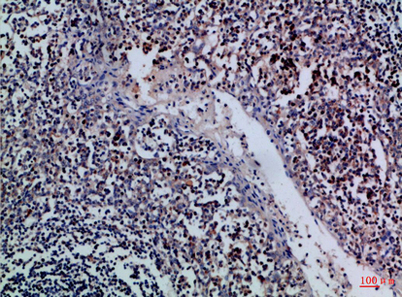

Recomended Dilution IHC-p 1:50-200, ELISA 1:10000-20000

IHC